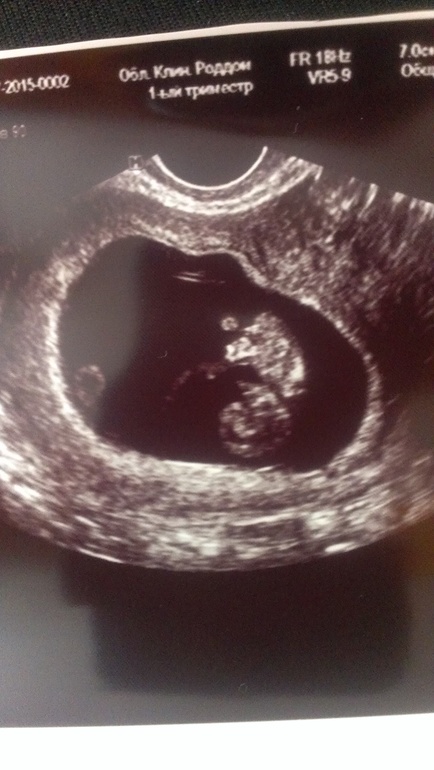

На сроке 9 недель и 4 дня сделали очередное узи, увидели один плод и ни намека на второй. В прошлый раз два врача узи сказали, что у меня двойня. Где они увидели два сердца непонятно=( Даже ктр второго плода написали. Смущало, только то, что я сама второе сердце не слышала.

Радует тот факт, что мы растем в соответствии со сроком, плаваем как космонавт перебирая ножками и ручками)))) Жду скрининг в 12 недель и нас выпишут. Вот такие дела.